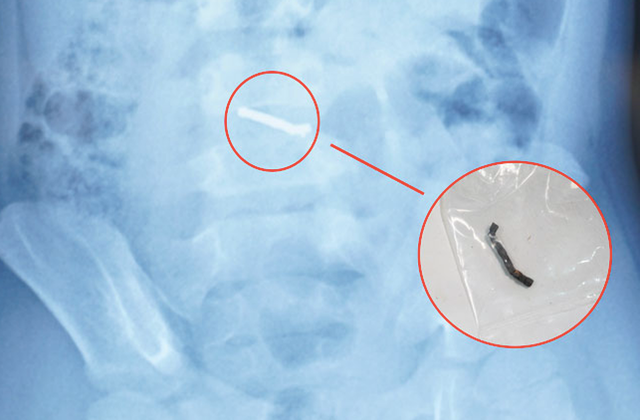

Trong thời gian dùng thuốc tại nhà, các triệu chứng không cải thiện, trẻ được tái khám và chụp X-quang phát hiện dị vật trong ổ bụng. Sau đó, trẻ được chuyển đến Bệnh viện Nhi Trung ương để tiếp tục theo dõi và điều trị.

Từ thông tin gia đình cung cấp về loại đồ chơi có các viên nam châm nhỏ có thể hút vào nhau, các bác sĩ chẩn đoán trẻ đã nuốt phải nhiều viên nam châm trong nhiều thời điểm. Sau khi xác định dị vật có từ tính và không thể tự đào thải ra ngoài, các bác sĩ đã tiến hành phẫu thuật cho trẻ.

Trong quá trình phẫu thuật, các bác sĩ phát hiện nhiều viên nam châm nhỏ dính vào nhau thành một chuỗi, gây thủng ruột. Các bác sĩ phẫu thuật đã tiến hành lấy dị vật, khâu lỗ thủng và đặt dẫn lưu. Sau 4 ngày, bệnh nhi đã sinh hoạt bình thường, bắt đầu được tập ăn trở lại và dự kiến sẽ được ra viện trong một vài ngày tới.